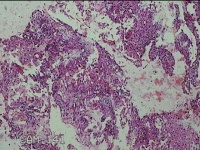

宫腔内容物

性别

女

年龄

30岁

临床诊断

疤痕妊娠 肝内结节 右肾囊肿

一般病史

停经49天,阴道流血1天。

标本名称

大体所见

子宫疤痕切口处见少许孕囊组织及凝血块。

绒毛及蜕膜组织。